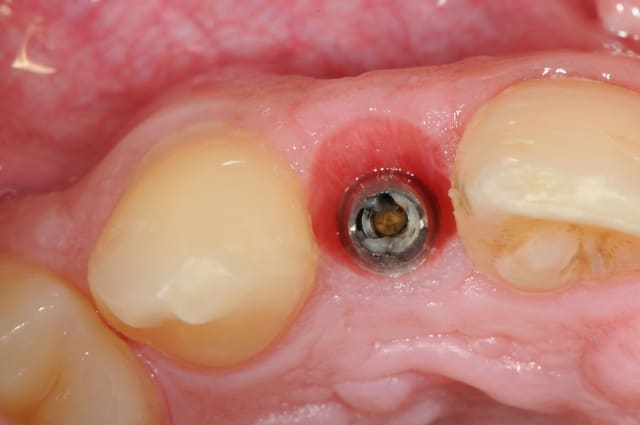

-cicatrisation de la première vis de cica,

-diamètre plus gros pour la vis de cica

- pilier pour la provisoire

- provisoire moule ION

- ajustage

- polissage soigneux

la suite tout à l'heure, ça sonne à la porte...